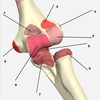

1

Not at all

2

3

4

5

Perfectly

14

Q

A

Flexor capri ulnaris

medial epicondyle (humerus) + olecranon -> pisiform/hamate/5th MC

flexion and adduction of the wrist

ulnar nerve